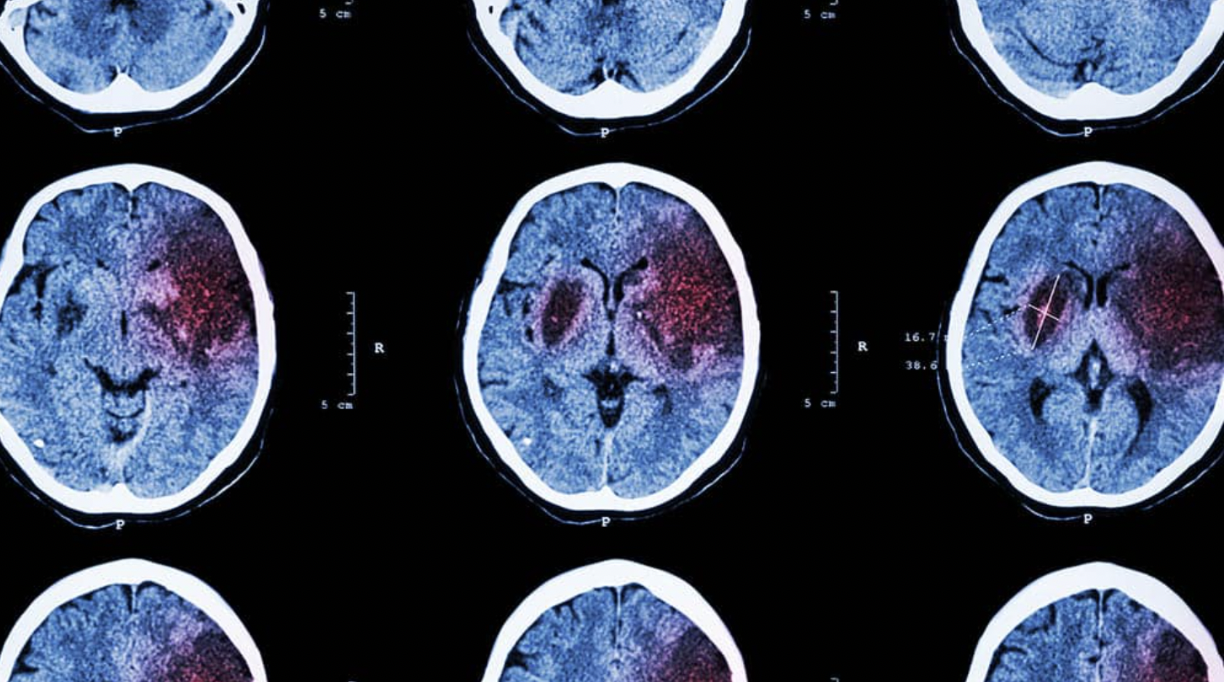

Evidências para o uso da cannabis na Isquêmia Cerebral e os benefícios dos terpenos

Isquemia cerebral : cannabis e terpenos no tratamento Os tratamentos atuais para isquêmia cerebral ou acidente vascular encefálico, que respondem por 6,5 milhões de mortes globais anualmente, continuam insuficientes para o tratamento de incapacidades e mortalidade. Uma característica marcante do Acidente Vascular Cerebral é a resposta inflamatória após o infarto, que leva a danos significativos após […]